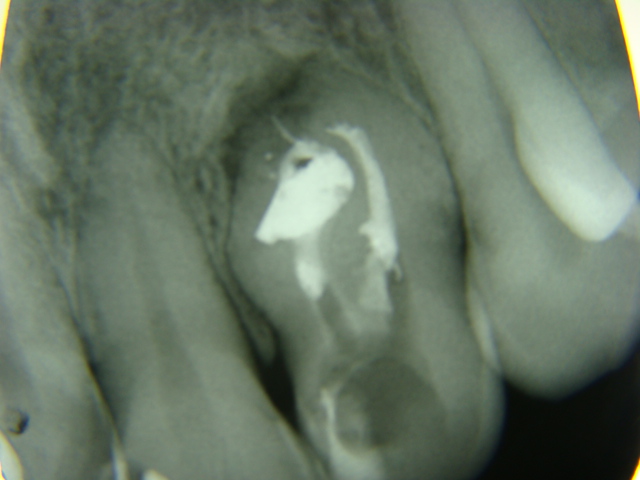

Me parece um dens in dens.Dente 22 com fistula e lesao periapical. Fiz a abertura coronaria e localizacao dos canais, preparo biomecanico com instrumentacao rotatoria Protaper e irrigacao com NaOCl 2,5% e EDTA 17%, curativo com pasta de hidroxido de calcio associada com iodoformio e Rx para poder visualizar a conformacao do canais.

O curativo permaneceu por 30 dias e fiz a obturacao dos canais, utilizando tecnica hibrida de Tagger. Manterei controle radiografico e Avisei a paciente que talvez seja necessaria uma intervencao cirurgica.